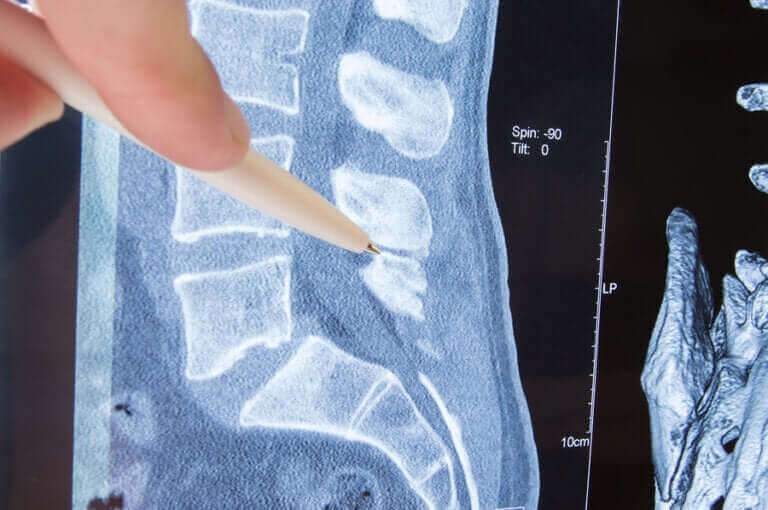

La colonne vertébrale est une structure osseuse formée par des vertèbres qui, à leur tour, protègent la moelle et nous permettent de nous déplacer librement. Les vertèbres ont des trous de chaque côté, d’où sortent les nerfs qui vont vers les différentes parties de notre corps.

La partie du nerf qui sort de la vertèbre est appelée “racine nerveuse”. Une radiculopathie est une compression du nerf, précisément dans la racine nerveuse. Quelles en sont les causes ? Quelles sont ses manifestations cliniques ? Nous vous aidons à résoudre ces questions et vous informons sur son traitement.

Radiculopathie lombaire

Elle correspond à la colonne lombaire. Les nerfs de cette région contrôlent les muscles et la sensibilité de la peau, des fesses et des hanches jusqu’aux pieds. Par conséquent, les symptômes de la radiculopathie lombaire sont généralement ressentis dans le bas du dos, les hanches, les jambes et le pied.

Dans les cas les plus graves, le contrôle du sphincter est compromis. Si la compression se produit à la sortie du nerf sciatique, le symptôme le plus courant est une douleur qui va du bas du dos à la plante du pied et descend le long de l’arrière de la jambe. C’est ce qu’on appelle la sciatique.